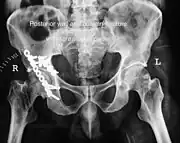

Fracture of the acetabulum

Posterior wall fracture as seen on 3-D CT scan